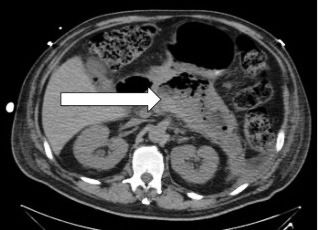

The physical examination was unremarkable except for a blood pressure of 80/60 mm Hg, which corrected with infusion of 2 L of normal saline. Laboratory findings included normal values for a complete blood cell count, complete metabolic panel, and serum amylase/lipase. CT of the abdomen and magnetic resonance cholangiopancreatography revealed acute emphysematous pancreatitis with extensive pancreatic necrosis (> 60%), without evidence of gallbladder or biliary tract disease (Figures 1 and 2).

Figure 1